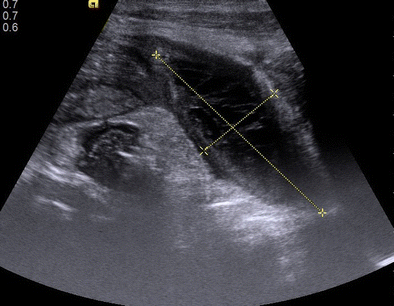

Fig. 1

Shows a defect in the superior wall of the sludge filled gallbladder (the “hole sign”)